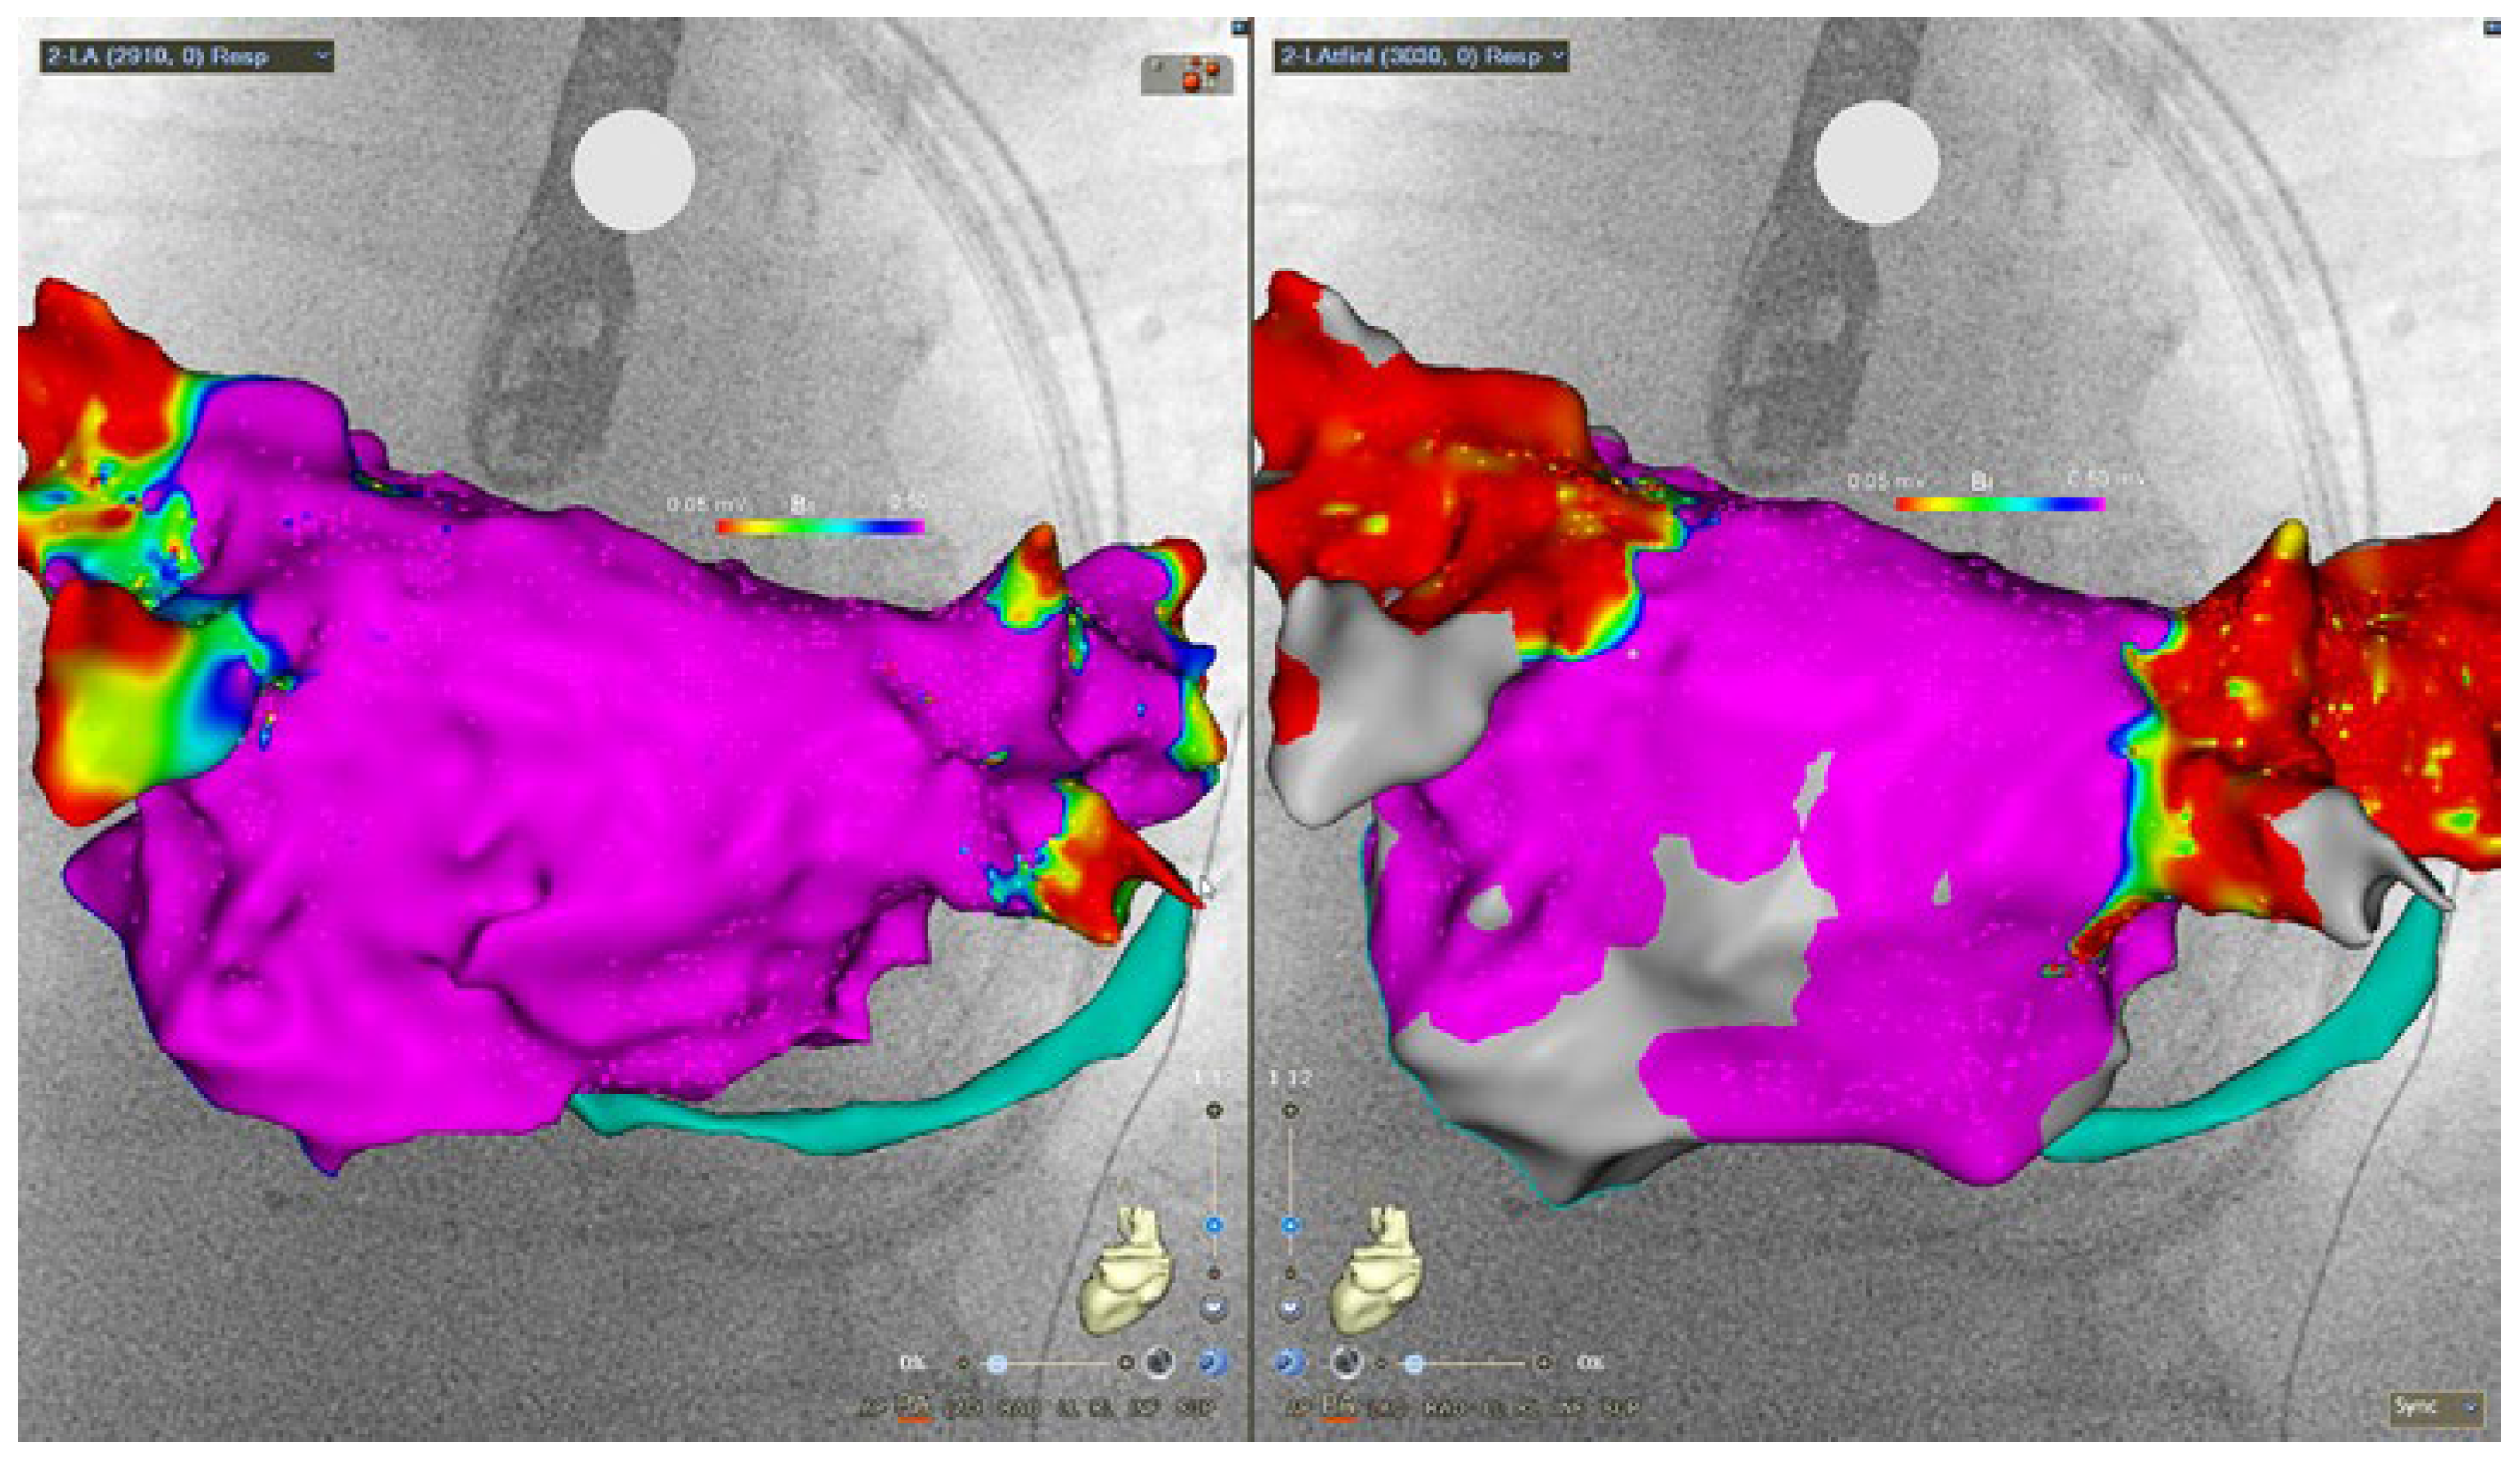

Case description